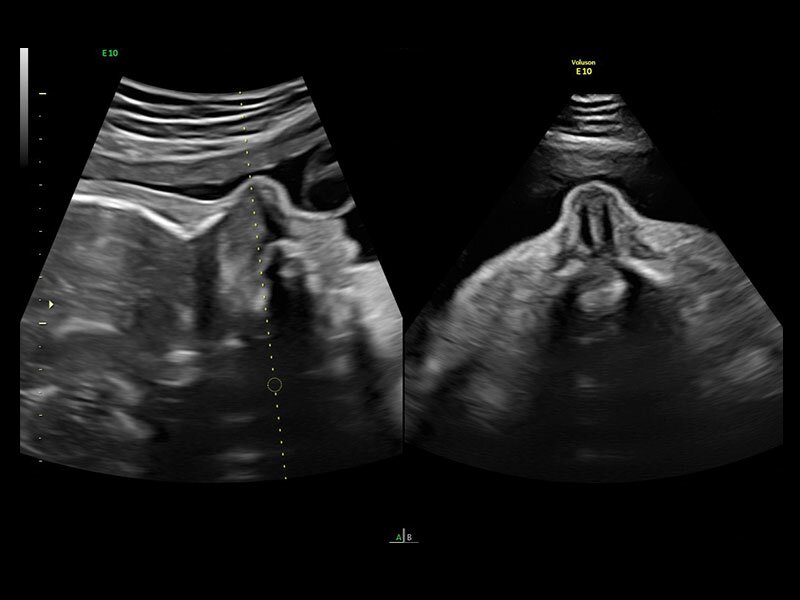

Клинические изображения

Четкие и подробные изображения

В медицинском учреждении, которое работает в условиях высокой нагрузки, значение имеет каждая минута. У врача нет времени подолгу корректировать параметры настройки, чтобы добиться наилучшей детализации изображения. Инновационная архитектура УЗИ аппарата Voluson E10 избавляет вас от лишних хлопот, — вы сразу получаете безукоризненную картинку. Вам не придется тратить лишнее время и силы: качество визуализации безупречно в любом режиме — от двумерных изображений до новейших 3D/4D технологий.

Современные клинические приложения и высокое качество изображений позволяют использовать Voluson E10 для наблюдения за ходом беременности максимально эффективно. С помощью этого аппарата можно проводить любые исследования, как рутинные, так и комплексные, выявляя проблемы на ранних стадиях и принимая своевременные меры.

• Усовершенствованный режим объемной визуализации с контрастированием (Volume Contrast Imaging, VCI) и опция OmniView

• Повышает контрастное разрешение и улучшает визуализацию области интереса в любой плоскости сечения, даже при исследовании структур неправильной формы.

• SonoVCAD heart (Sonography-based Volume Computer Aided Display heart) — программа формирует изображения сердца плода в стандартных проекциях в соответствии с международными рекомендациями на основе одного объемного изображения или данных 4D визуализации, полученных методом STIC.